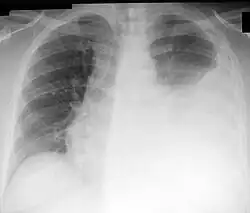

Pleuraergüsse können einseitig oder (meist bei kongestiver Herzinsuffizienz) beidseitig vorhanden sein, was meist nach dem Röntgenbild beurteilt wird. Vermuten kann man einen Erguss bei einem „Nachschleppen“ einer Seite, verbreiterten und eventuell auch vorgewölbten Zwischenrippenräumen bei der Atmung, einer Dämpfung des Klopfschalls und einer (basalen) Abschwächung bzw. einem Fehlen des Atemgeräuschs[2]:S. 378 f. sowie des Stimmfremitus, der wie die Bronchophonie stark abgeschwächt bis aufgehoben ist, über einem Lungenabschnitt.[4]

Bei beidseitiger basaler Abschwächung, gestauten Halsvenen, peripheren Ödemen, Tachykardie und drittem Herzton besteht der Verdacht auf einen kardial bedingten Pleuraerguss. Ein Pleurareiben kann zu Beginn eines Ergusses im Rahmen einer Lungenentzündung (Pneumonie) mit Brustfellentzündung (Pleuritis) zu hören sein. Bei einseitiger Dämpfung ist die Wahrscheinlichkeit eines Exsudates höher und die Diagnose meist schwieriger. Nachweisen lässt sich ein Pleuraerguss am schnellsten und genauesten durch eine Ultraschalluntersuchung des Brustkorbs, womit bestimmte Strukturen (pleurale Septen) besser sichtbar werden als mit einer Computertomografie. Bei intensivpflichtigen, insbesondere beatmeten, Patienten ist die Ultraschalluntersuchung zudem vorteilhafter als eine in Rückenlage des Patienten durchgeführte Röntgen-Thorax-Aufnahme.[2]:S. 379–381

Auf der beim Verdacht auf das Vorliegen eines Pleuraergusses empfohlenen Röntgenaufnahme des Brustkorbs sind Pleuraergüsse in der p.-a.-Thoraxaufnahme meist ab einem Volumen von 200–300 ml, bei der seitlichen Aufnahme ab 50 ml erkennbar.[2]:S. 380 Typisch ist bei einer im Stehen angefertigten Aufnahme eine nach lateral (außen) ansteigende Verschattung (dargestellt durch die den Erguss begrenzende Damoiseau-Ellis-Linie, auch Ellis-Damoiseausche Linie[5] genannt[6]).